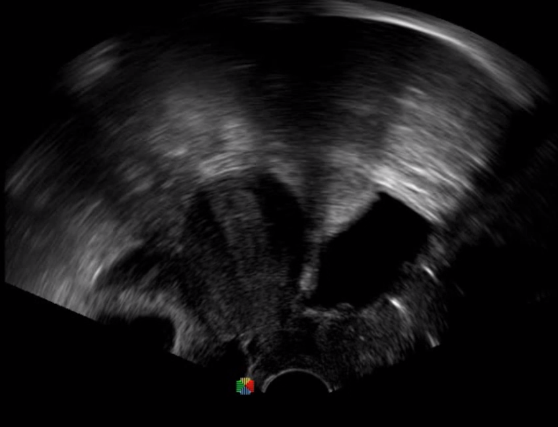

傳統(tǒng)腔內(nèi)探頭采用直柄設(shè)計(jì),在搭配穿刺架使用時(shí),手術(shù)空間小,不易操作;生殖專用的曲柄探頭,探頭柄采用彎曲成角度設(shè)計(jì),可實(shí)現(xiàn)監(jiān)視、取卵兩不誤,搭載穿刺架時(shí),可以清晰顯示穿刺針的進(jìn)針過(guò)程、深度和位置,實(shí)時(shí)監(jiān)視取卵全過(guò)程,保障取卵操作精準(zhǔn)與安全。

取卵臨床圖